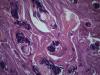

Опухоль матки |

Плоскоклеточный умереннодифференцированный рак,инвазия в железы.